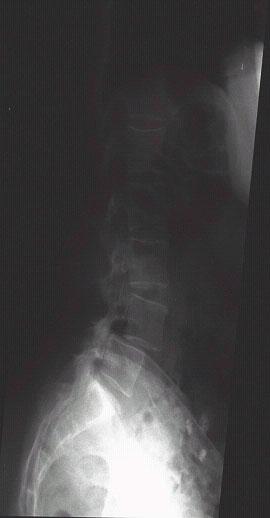

Abb:1- 3

59jährige Patientin mit einem Wirbelgleiten zwischen dem 4. und 5. Lendenwirbelkörper und einer daraus resultierenden Einengung des Wirbelkanals (Pseudospondylolisthese bei Spinalkanalstenose. Normales seitliches Röntgenbild (links), Kernspintomographien (mitte und rechts).